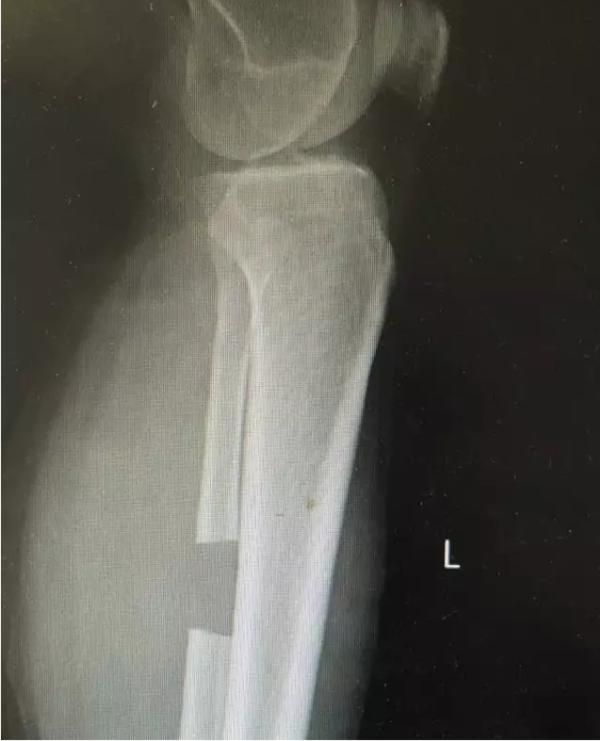

膝关节不均匀沉降术后患者X线片(下图)

术前片:

术后图如下: